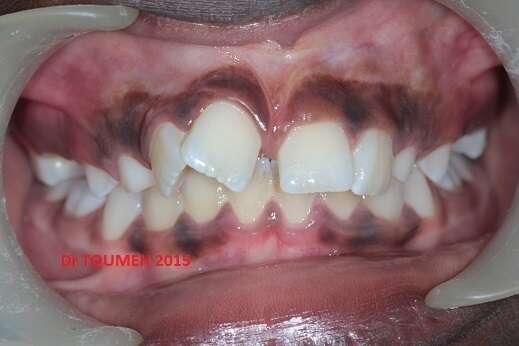

Canines incluses , traitement orthodontique 731

L'acte chirurgical de dégagement des canines incluses a été réalisé par le Dr BERTAUD

Avant